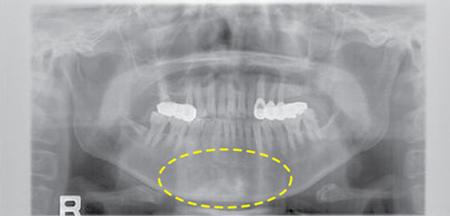

위아래 턱뼈, 전치아를 한 번에 촬영하여 구강위생 상태를 평가할 수 있는 사진으로 구강암 환자들은 대부분 촬영하게 됩니다.

[파노라마 사진]

파노라마(Panorama)사진으로 전반적인 구강상태 및 구강암에 의한 턱뼈 침범여부를 일차적으로 알 수 있습니다.